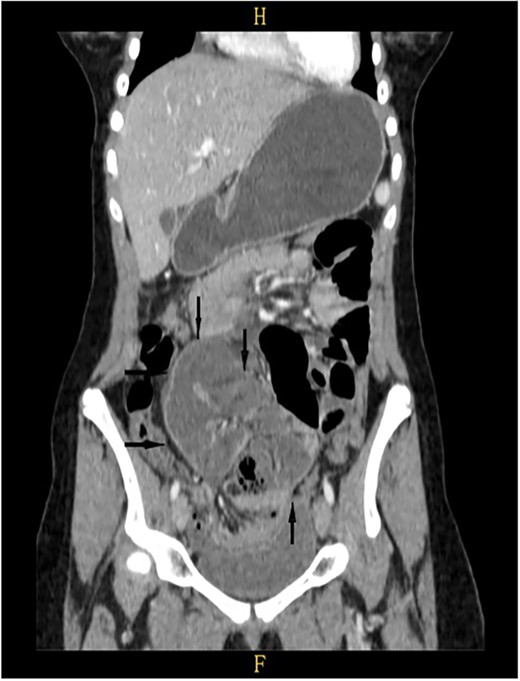

On a retrospective review of our patient’s ECT, we recognised a membrane encapsulating the small intestine centrally, which indicates the diagnosis of ACS (Figs 4 and 5).

Retrospective review of ECT (coronal section), a membrane encapsulates the small intestine centrally indicates the diagnosis of ACS (black arrows).